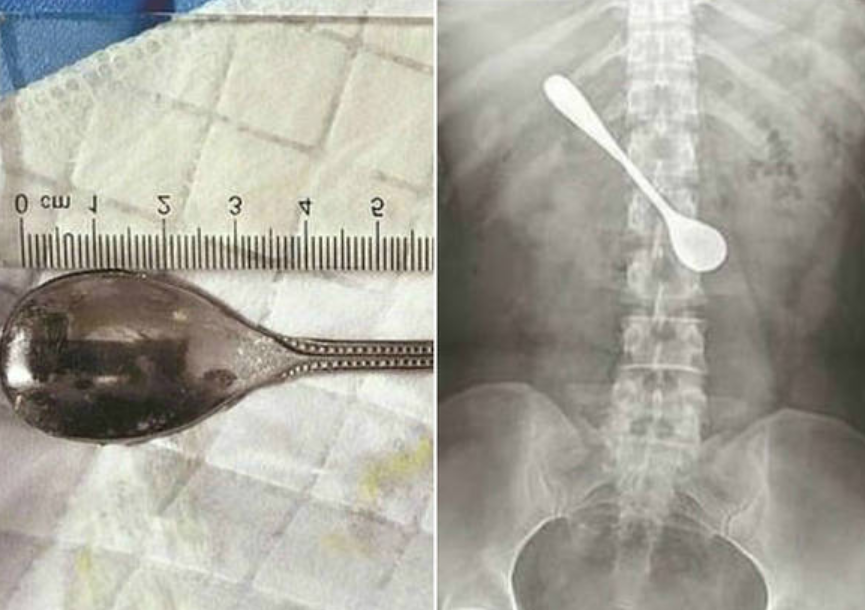

Mulher fica com colher no intestino após engasgar com peixe

23/04/2019 às 09h42